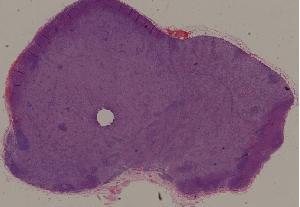

28. Adenoma of the colon